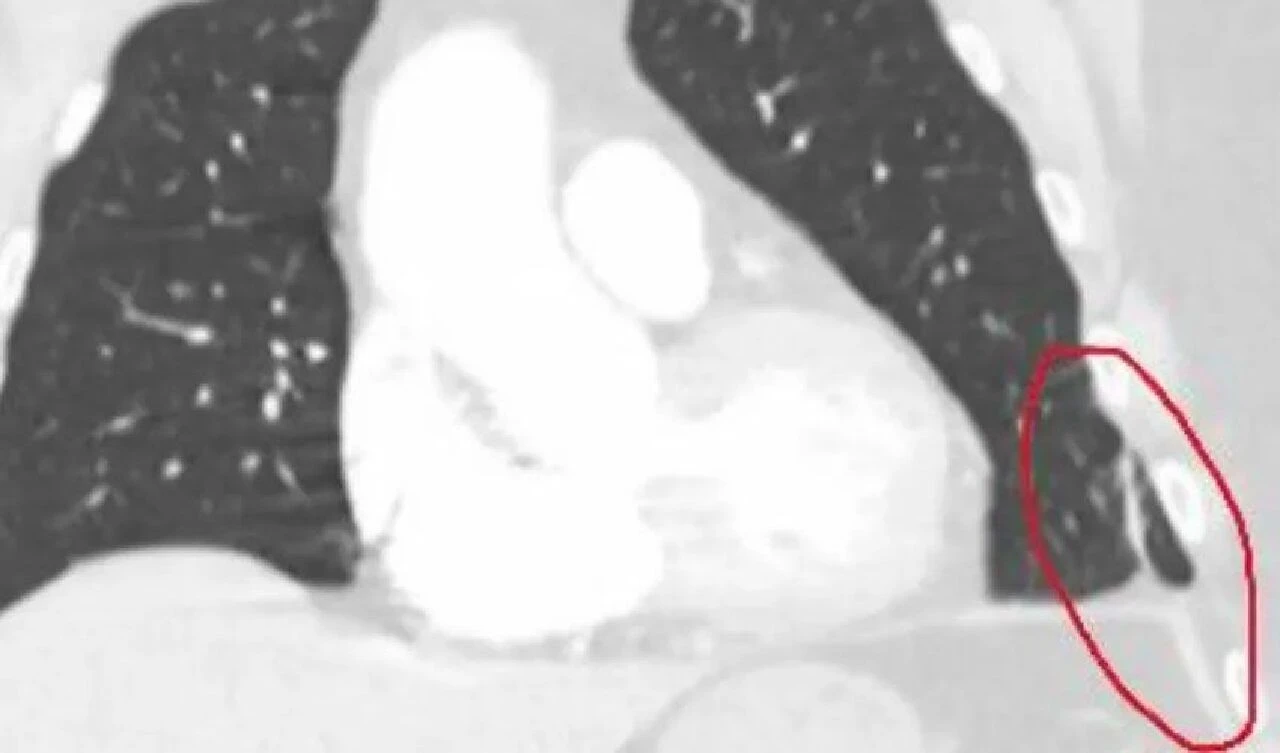

''Hatırladığım bir sonraki şey, burnumda tüpler olan bir hastane yatağında olduğum ve bilincimin gidip geldiğiydi. Yan tarafımdaki bandajın altından kanlı bir sıvı akan bir tüp vardı."